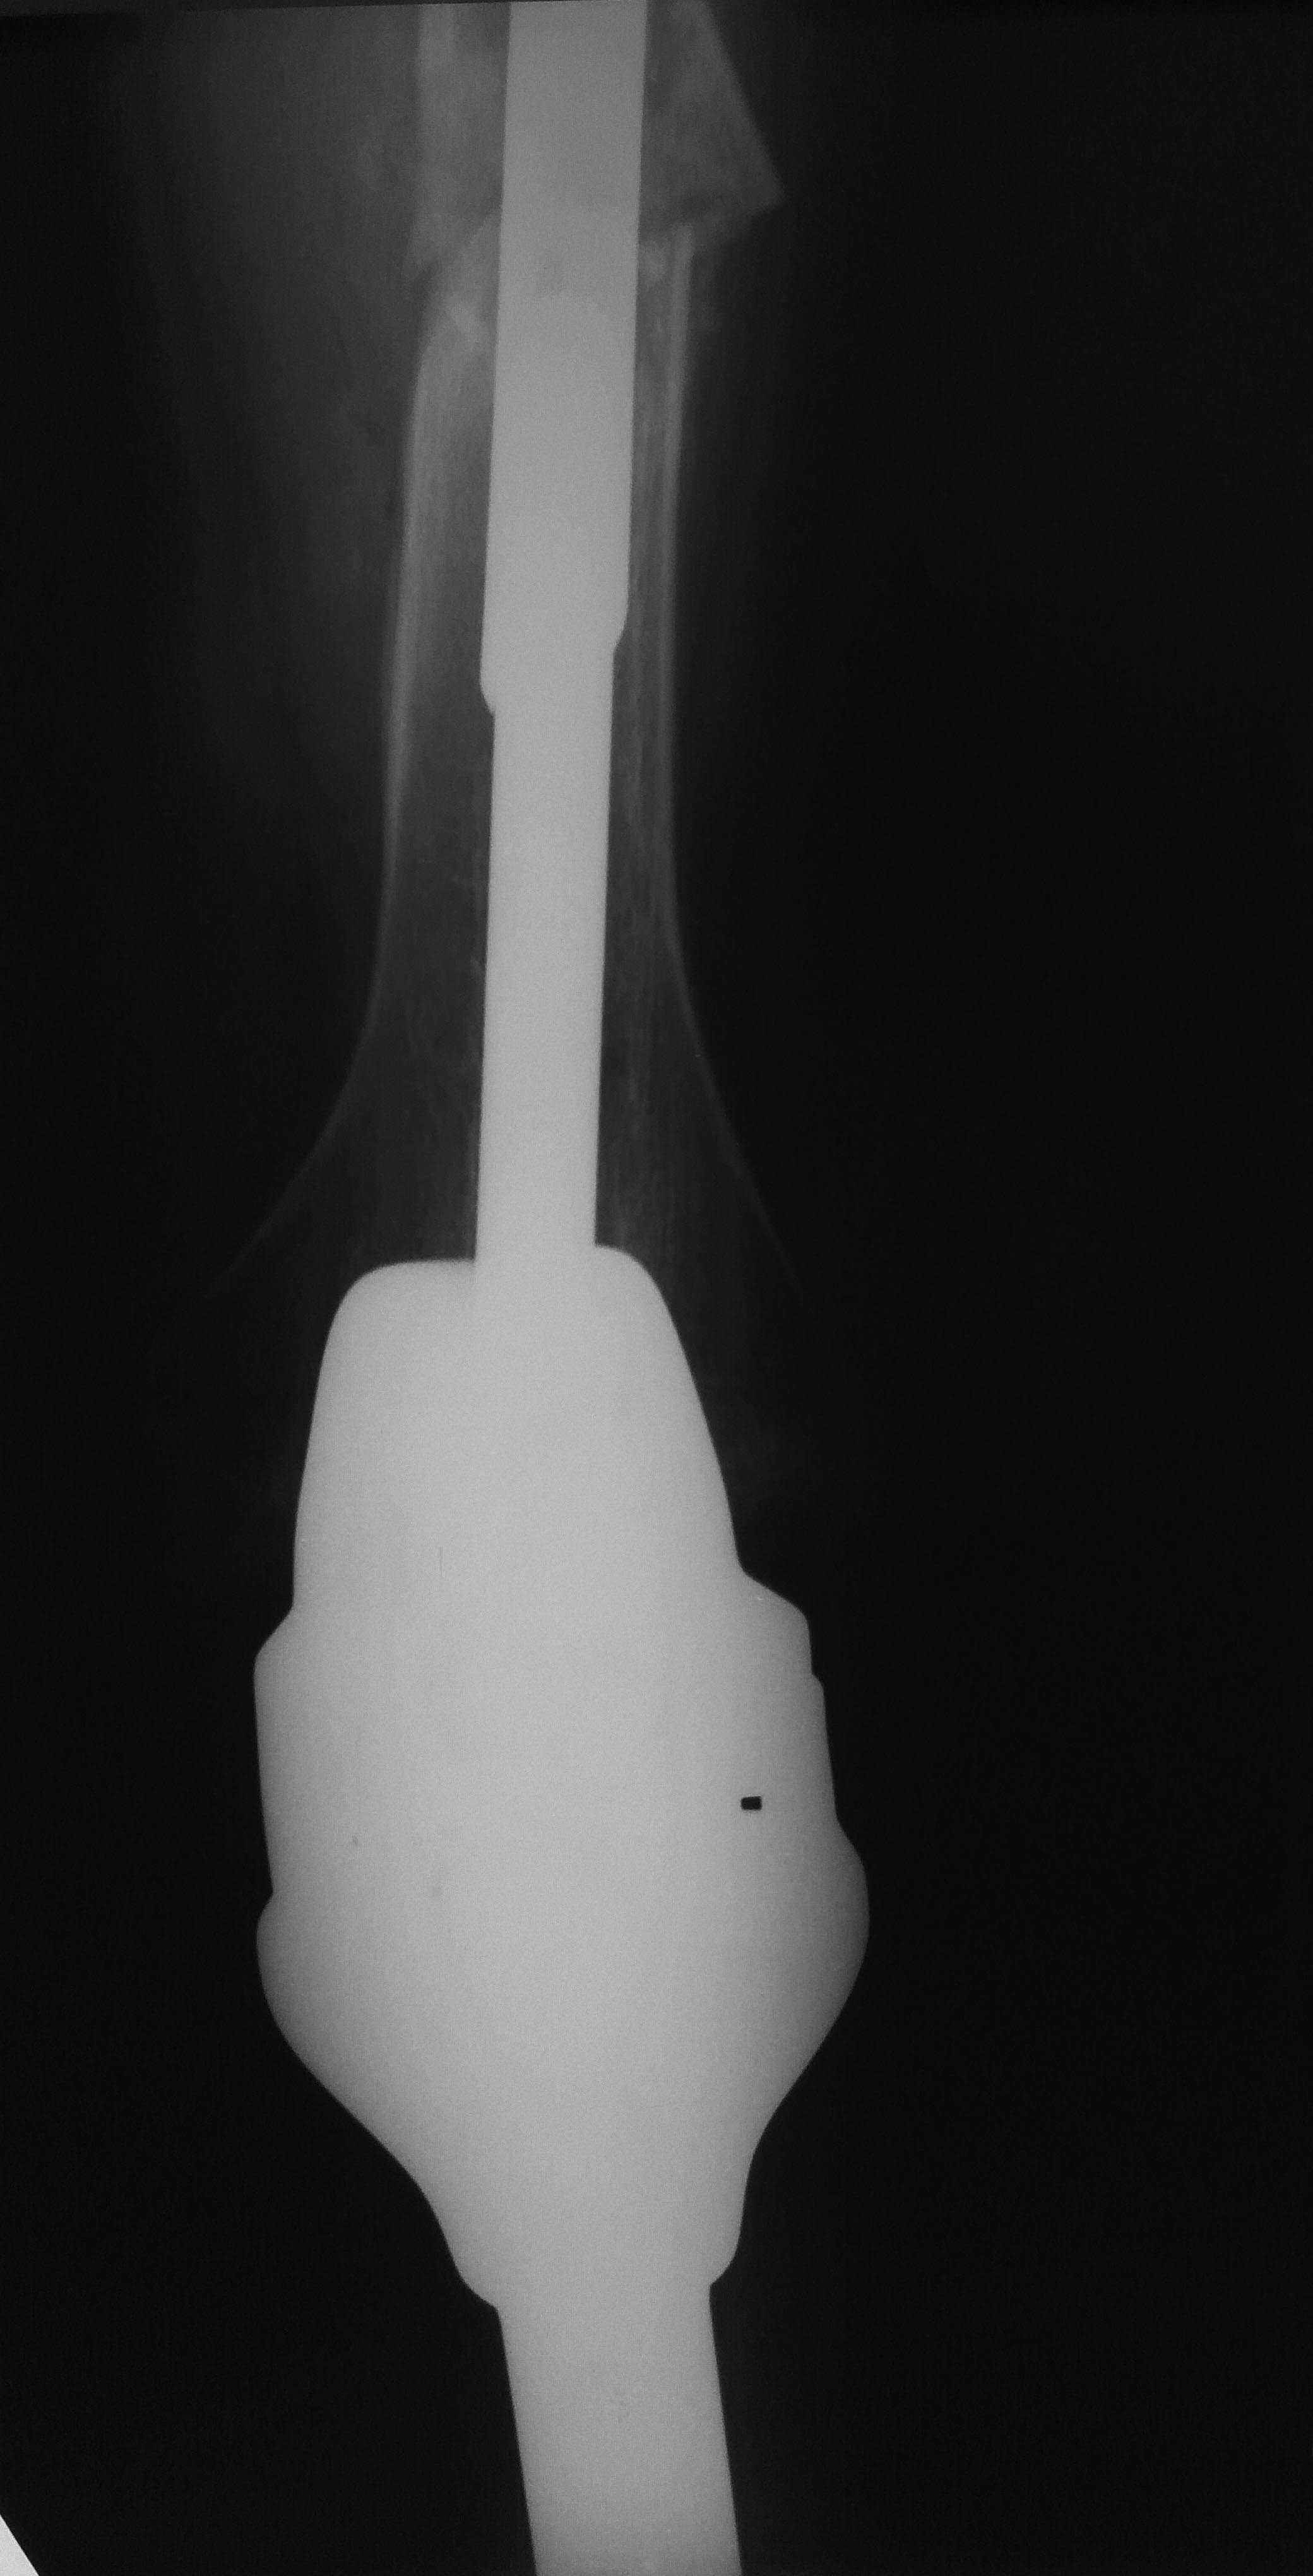

Все прошло по плану. Длину восстановили дистрактором. Пришлось сделать

небольшую чрескожную остеотомию, чтобы устранить смещение по ширине.

Обратила на себя внимание наружная ротация стопы по отношению к колену.

И получилось ее устранить с небольшим усилием. То есть присутствует еще

и нестабильность большеберцового компонента. Есть ли какие-то мысли, как

ее устранить, не меняя эндопротез?